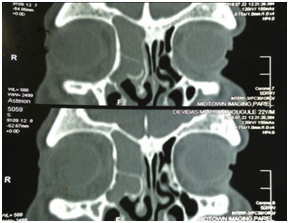

A 22years old male presented with bilateral blocked nose sensation (right>left) since 7-8months, persistent frontal headache. History of right sided facial heaviness and pain with right periorbital swelling. No history of trauma, clear fluid discharge from nose. No history of recurrent episodes of upper respiratory tract infections/ recurrent episodes of sneezing/running nose or any previous trauma. On examination, anterior rhinoscopy showed mucopurulent discharge and crusting, nasal endoscopy showed bilateral inferior turbinate hypertrophy, mucosa was normal. CT scans of paranasal sinuses showed large homogenous expansile cystic lesion obstructing the right frontal sinus drainage. Another homogenous mass was noted in extending to the right ethmoid sinus suggesting the possible diagnosis of two separate frontal and ethmoid mucoceles with pansinusitis and right sided proptosis (Figure 1-3).

Figure 1 & 2 CT scans showing homogenous masses in the right frontal and ethmoid sinuses.

Figure 3 CT scan suggestive of right side proptosis.